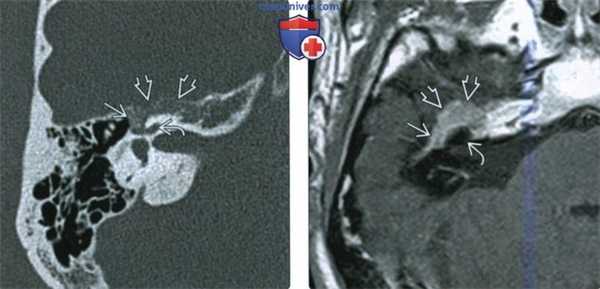

(Слева) При корональной МРТ Т1 ВИ С+ FS у пациента с кондуктивной тугоухостью и подергиванием мышц лица определяется мультифокальная контрастирующаяся ШЛН, проникающая в ячейки сосцевидного отростка и книзу вдоль сосцевидного сегмента ЧH VII.

(Справа) При аксиальной МРТ Т1 С+ визуализируется контрастирующееся образование, выбухающее в медиальные отделы средней черепной ямки из большого поверхноаного каменистого нерва. Диагноз ШЛН можно заподозрить при распространении по ходу барабанного и лабиринтного ЧН VII во внутренний слуховой канал.